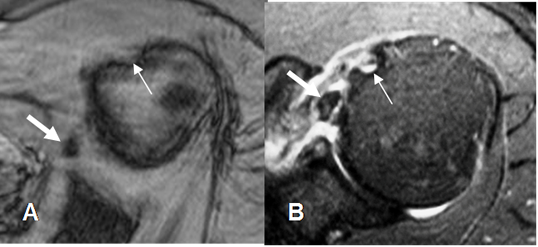

Fig 156. Luxación del biceps.

A: RM axial en FFE y B: RM coronal en STIR. “Luxación” medial de la cabeza larga del biceps. (Flecha delgada), con ruptura retraída del tendón del subescapular. (Flecha gruesa).